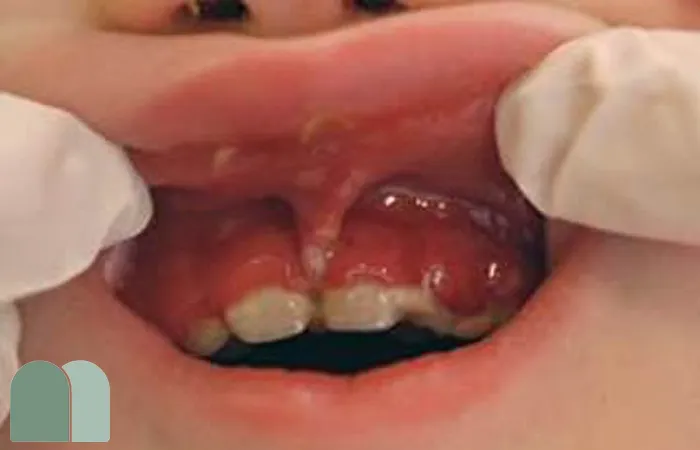

قرمزی و تورم لثهها

لثهها معمولاً قرمز و متورم میشوند و در برخی موارد ممکن است خونریزی نیز داشته باشند.

این علائم به شدت کودک را آزار میدهد.